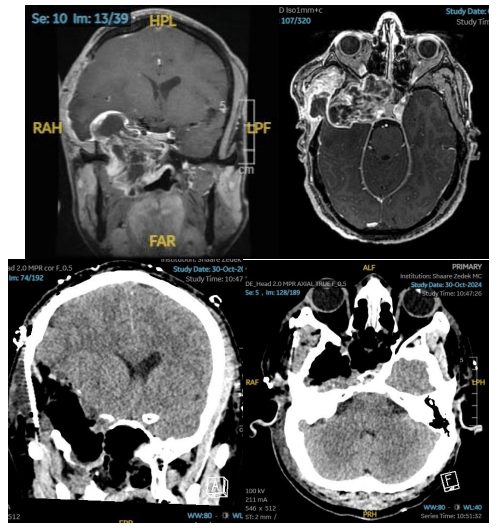

"המטופל הגיע עם גידול המערב את בסיס הגולגולת, את החלק המוחי התוך גולגולתי וגם את חללי האף", סיפר ד"ר מרגלית. "כיוון שהגידול היה מאוד גדול, הוא החל להרוס חלק משמעותי מבסיס הגולגולת. הכריתה שלו חייבה אותנו לפעול בשתי גישות ניתוחיות בו זמנית. גישה אחת דרך פתיחה של הגולגולת, מה שנקרא קרניוטומיה, וגישה שנייה אנדוסקופית דרך האף.

"לאחר התייעצות החלטנו לבצע את שתי הגישות באותו ניתוח, וכך הצלחנו להוציא את כל הגידול משני הצדדים בניתוח אחד ולחסוך למטופל ניתוח מורכב נוסף", סיכם.